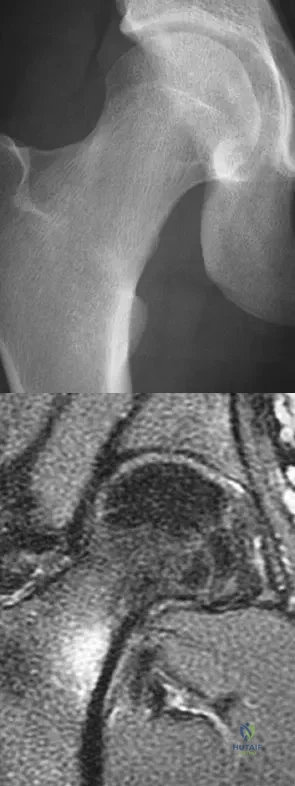

A 21-year-old collegiate female cross-country athlete reports right hip pain that begins about 12 miles into a run, followed by pain resolution when she discontinues running. However, each time she tries to resume a running program, she experiences recurrence of pain deep in the anterior groin. A plain radiograph and MRI scan are shown in Figures 8a and 8b. Management should consist of